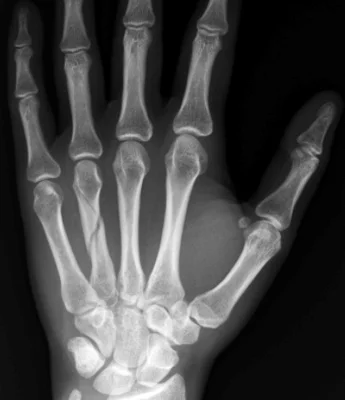

- Careful about rotational malalignment

- Check rotation by flexing the fingers

Finger malrotation

- Undisplaced / or only one MC

- Treatment by cast / or splint

- Displaced / Rotated / Multiple

- Treated by internal fixation (screws / plates / wires)